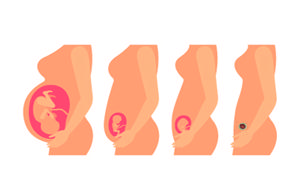

从国家放开二胎政策后,很多生了一个孩子的父母都在想一个问题,也是很多父母的疑虑,那就是到底要不要生第二胎呢?不生怕一个孩子以后会孤单,生又考虑到各种现实的问题,让人很是头疼,那么如何从长远看要不要生二胎呢?

怀孕晚期胎死腹中,导致胎死腹中的原因主要有母体和胎盘、脐带、胎儿等方面的因素。其中母体因素主要有孕妇全身的血氧含量降低和子宫胎盘局部血供不足。胎盘因素主要有胎盘功能障碍,如胎盘种植异常、胎盘形态异常、胎盘病理改变。脐带长度异常,脐带缠绕、脐带打结及扭曲、脐带血肿及阻塞、脐带附着异常。胎儿先天性疾病等。

准妈妈怀孕到了28周以后就称之为孕晚期,孕晚期宝宝的发育已趋健全,但医生一般还是建议要做一次孕晚期B超,孕晚期B超是什么呢?孕晚期B超一般是检查BB的发育情况,检查BB有无畸形,还可以检查胎盘的位置,有无前置胎盘等等一些异常情况,因此孕晚期B超是有必要检查的!

孕晚期了,越来越临近分娩,不过孕妈妈们可千万不能疏忽大意哦。孕晚期的注意事项还很多,而其中一个,就是要密切监测宝宝的胎动啦。胎动反应着宝宝的健康状况,一定要及时发现胎动异常的状况哦。孕晚期胎动频繁、胎动减少都反应了宝宝的变化,孕妈妈们一定要警惕啦。具体是怎么回事,要如何分辨呢?下面一起来了解下吧。

宫缩,言下之意就是子宫有规律的收缩。大概在宝宝降临前的一个月,宫缩就开始陪伴着准妈妈。随着宝宝到来的日子越来越近,准妈妈会开始感觉到不规则的宫缩,频率也会越来越高。作为分娩的重要标志,准爸妈们必须要了解孕晚期宫缩的细节,以最充分的准备迎接宝贝的到来。

怎么给孕晚期孕妇补钙